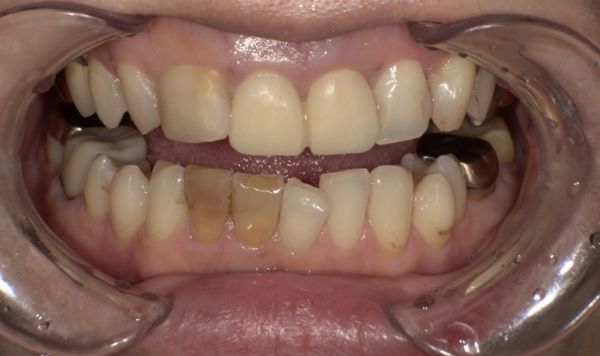

今回の患者様は、「前歯を過去に治療しセラミックにて修復をしたが、変色してしまったため交換したい」とのご希望があり来院されました。

他の隣り合う歯も形が気になっているので、形も含めご相談をしたいとのことでした。また、下の歯にも変色した保険の被せ物があり、これについても変更をご希望されました。

特に処置後も痛みなどはなく、状態も安定しています。色調にもご満足いただけました。

今回の症例では、前歯の色調に対する不満、過去に治療するか迷っていた歯に関する将来的な不安から、やり替え治療と新たな被せ物治療のご希望がありました。

今回の被せ物に関しては、セラミックでの治療なので、金属を使用していないため、歯と歯茎の境目に金属色が見えてくるなどのリスクもありません。セラミックの中でも、ジルコニアセラミックを使用することで色調だけでなく、汚れがつきにくく、強度もあり、長期的に使用可能な被せ物を装着することができます。また、ご自身の歯との色の違いを最小限にするように心がけました。